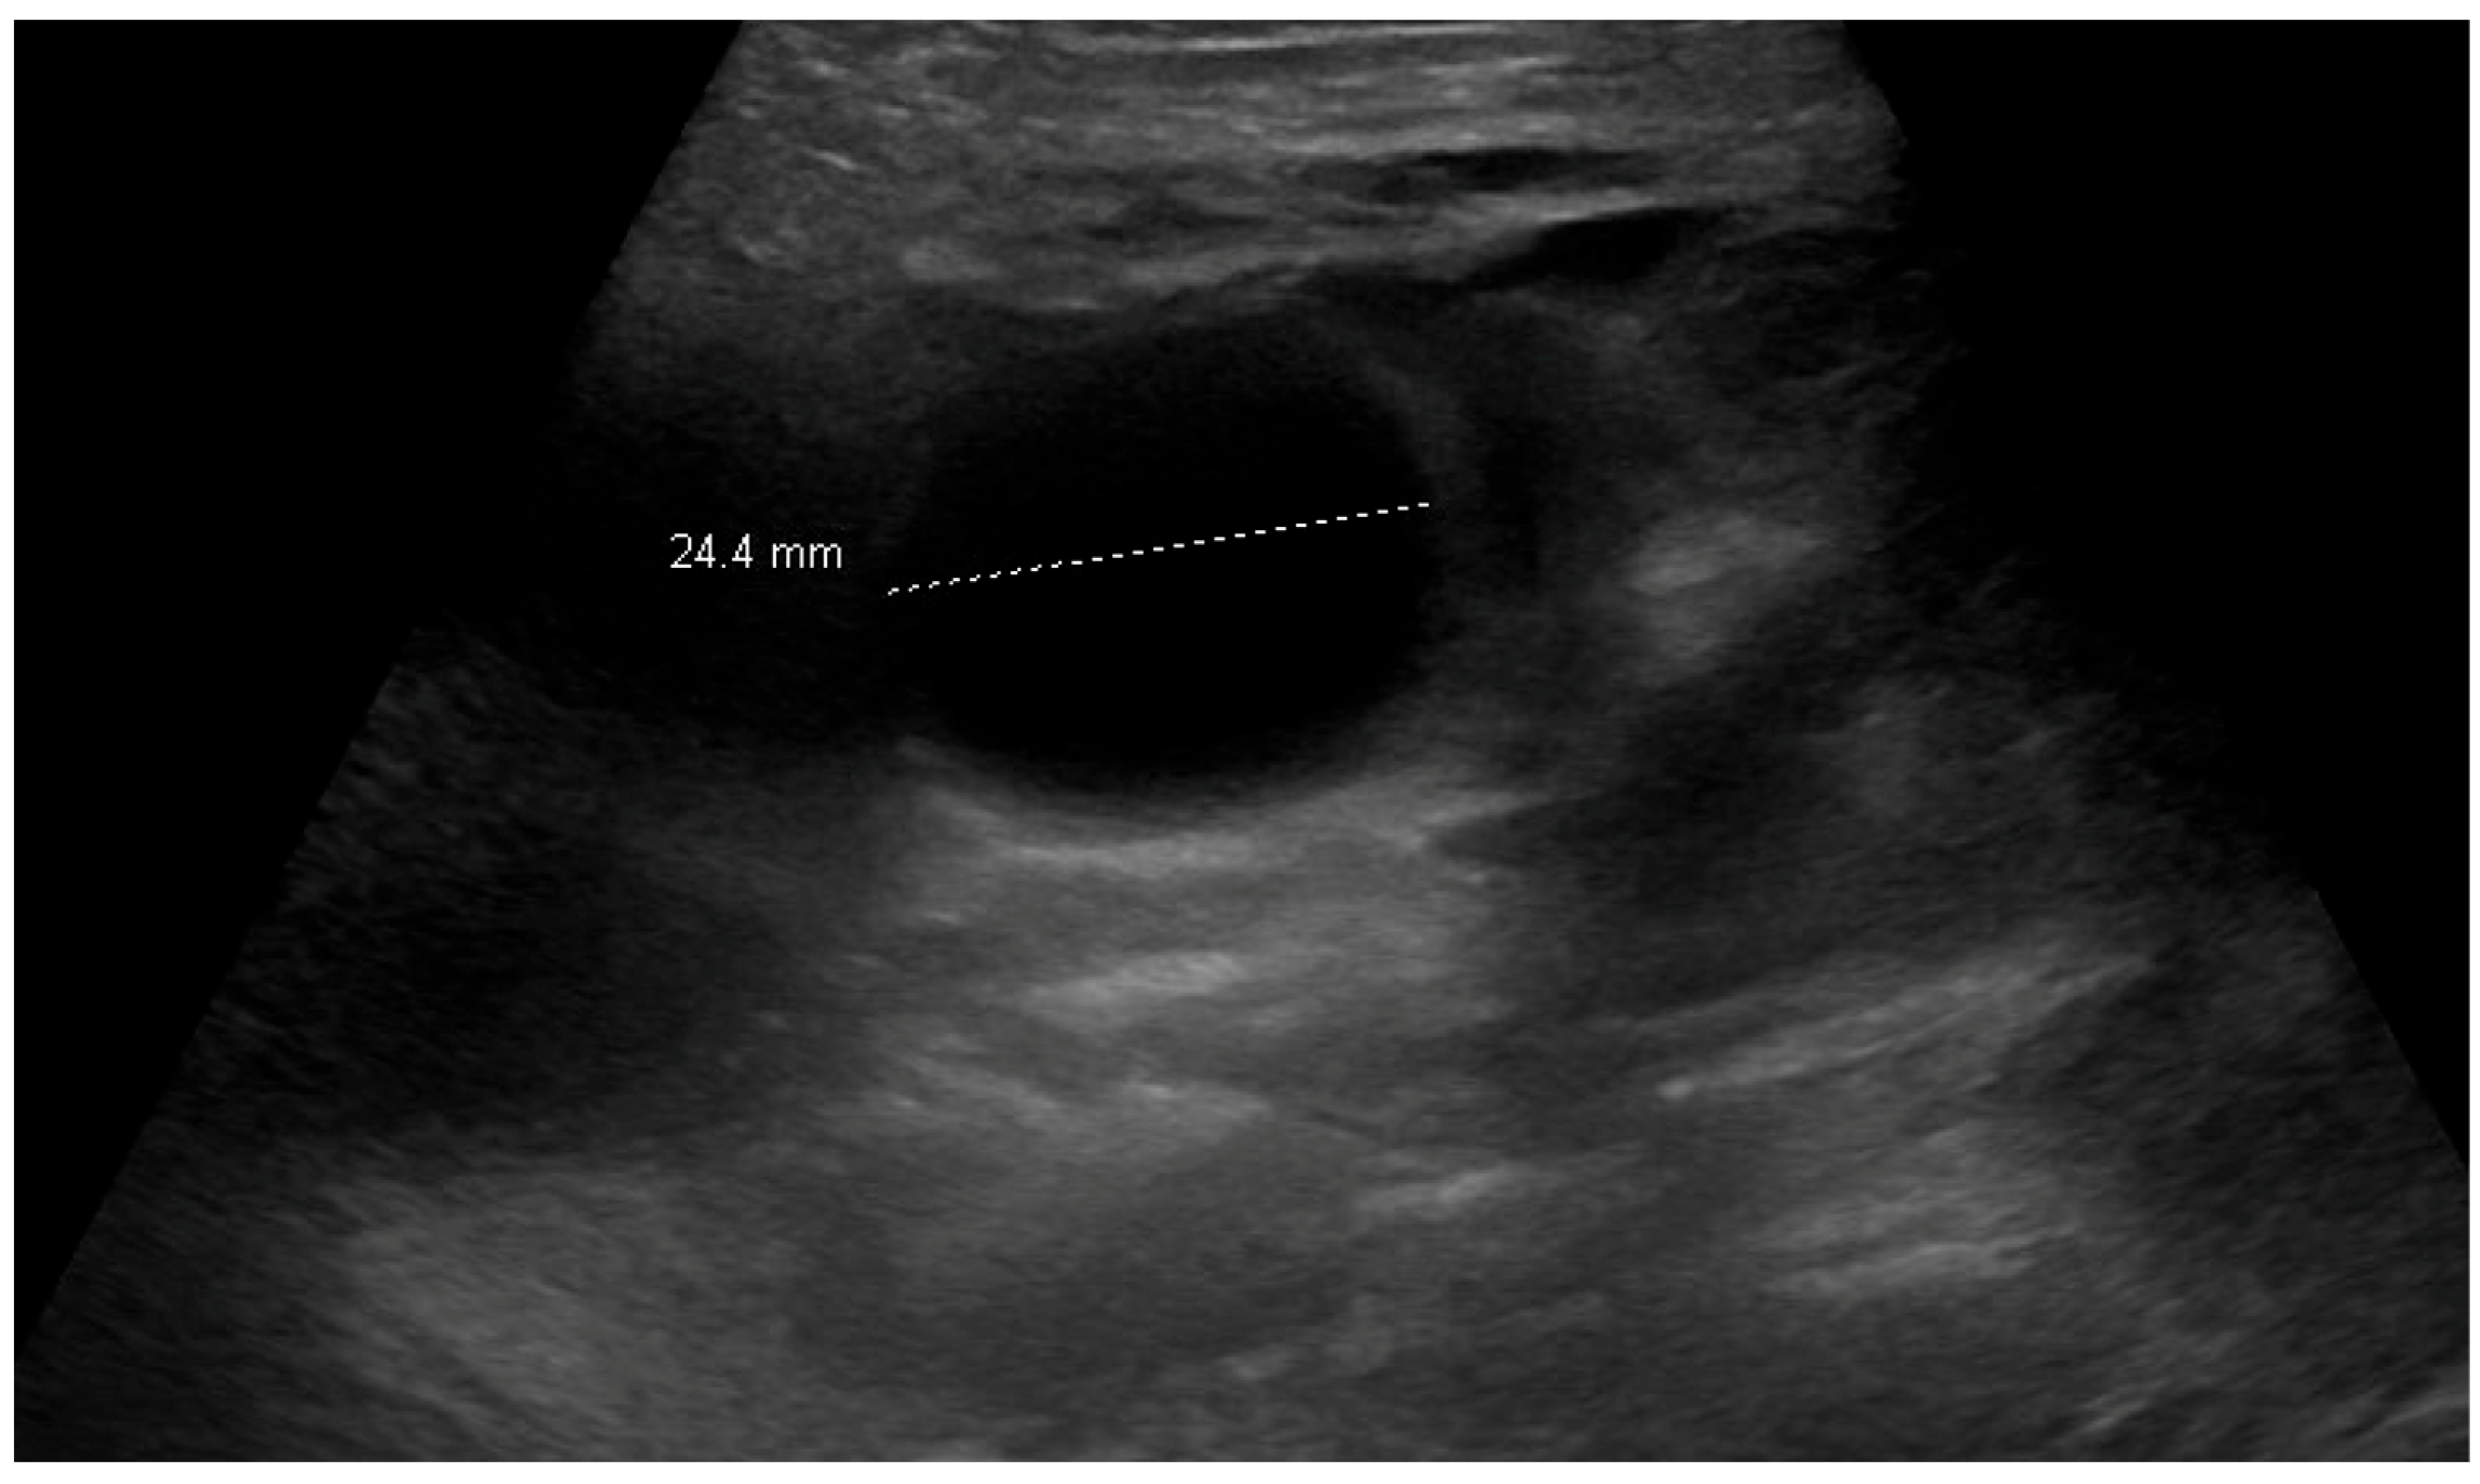

3.1. Patient 1

3.2. Patient 2

3.3. Patient 3